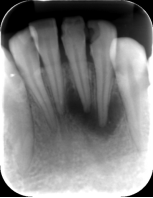

全口根尖片

根管治疗前中后